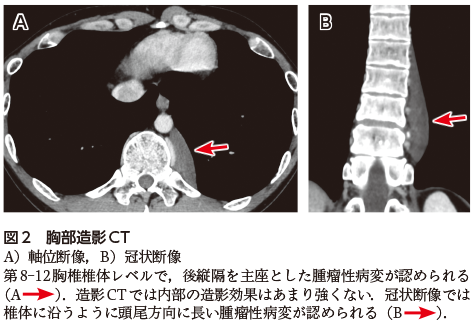

• A1:心陰影に重なって,第8-12胸椎左側に紡錘状の腫瘤影が認められる(図1A).腫瘤影の辺縁は左傍脊椎線(図1B)に連続しており,この部位では下行大動脈の外側縁(図1B)のシルエットが消失している(シルエットサイン陽性).

胸部単純X線写真(図1)では心陰影に重なる紡錘形の腫瘤影を認め,腫瘤影の辺縁は左傍脊椎線に連続している.また,腫瘤により下行大動脈外側縁が第8胸椎レベルより下方で不明瞭となっており,後縦隔を主座とする病変であることがわかる(図1B).

左傍脊椎線は下行大動脈の後方で傍脊椎脂肪組織が下葉の内側と接するために形成される線で,大動脈弓部より下方で認められる.胸部単純X線写真では椎骨左縁で椎体の1〜2 mm外側に平行に走行する線状影として認められる(若年者では傍脊椎脂肪織が少ないため,椎体の外側縁自体を見ていることも少なくない).この線が膨隆した場合は,後縦隔腫瘍やリンパ節腫大,感染性脊椎炎による傍椎体膿瘍などが疑われる.本症例では,腫瘤影の辺縁が下行大動脈の外側縁の膨隆ではないことに注意する必要がある.

図1